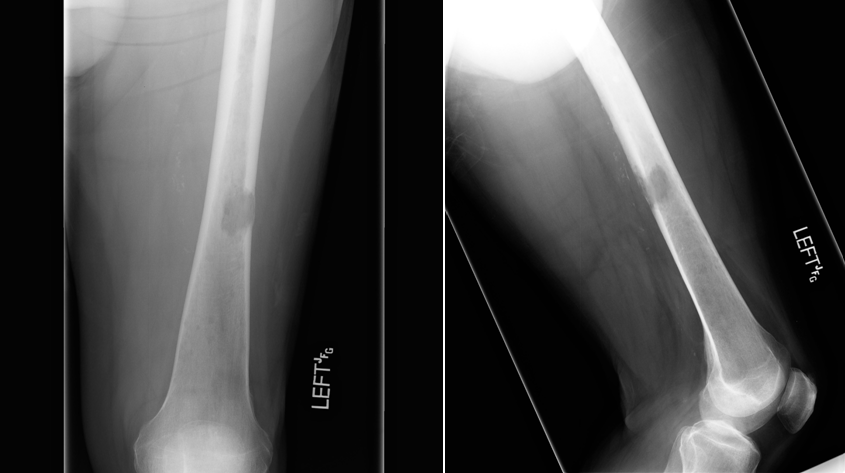

Learning Objectives: At the conclusion of the general orthopedic self-assessment exam physician assistants should be familiar with radiographic characteristics of benign and malignant bone tumors, be able to identify common benign bone tumors including enchondroma, unicameral bone cyst, nonossifying fibroma, osteoid osteoma, aneurismal bone cyst, giant cell tumor, and osteochondroma, be able to identify common malignant bone tumors including osteosarcoma, chondrosarcoma, and Ewing’s sarcoma, and be able to identify and understand treatment of pathological fractures from metastatic disease.